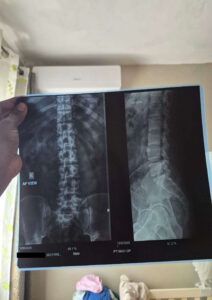

Varun, 31 ans, souffre d’une hernie discale cervicale dégénérative C4-5 avec radiculopathie. Financièrement, son traitement, son billet d’avion, son hébergement et son allocation de subsistance coûteront Rs 1,148,256 .